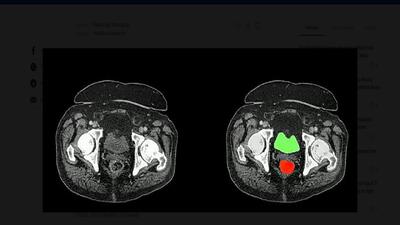

با افتتاح و بهرهبرداری از دستگاه پتاسکن (PET Scan) در هرمزگان، این استان به جمع معدود استانهای کشور پیوست که این خدمت تخصصی تصویربرداری پزشکی را با تعرفه دولتی به بیماران ارائه میدهند.

کردستان در ردیف ۶ استان برخوردار از دستگاه پتاسکن( تشخیص سرطان)

رئیس دپارتمان پزشکی هستهای پزشکی هستهای و تصویربرداری بیمارستان کوثر سنندج گفت: کردستان ششمین استاد کشور در دریافت دستگاه pet scan پیشرفته از نوع ۲۰۲۱ است که نشان از اهمیت و توجه به تجهیزات پزشکی پیشرفته در استان است.